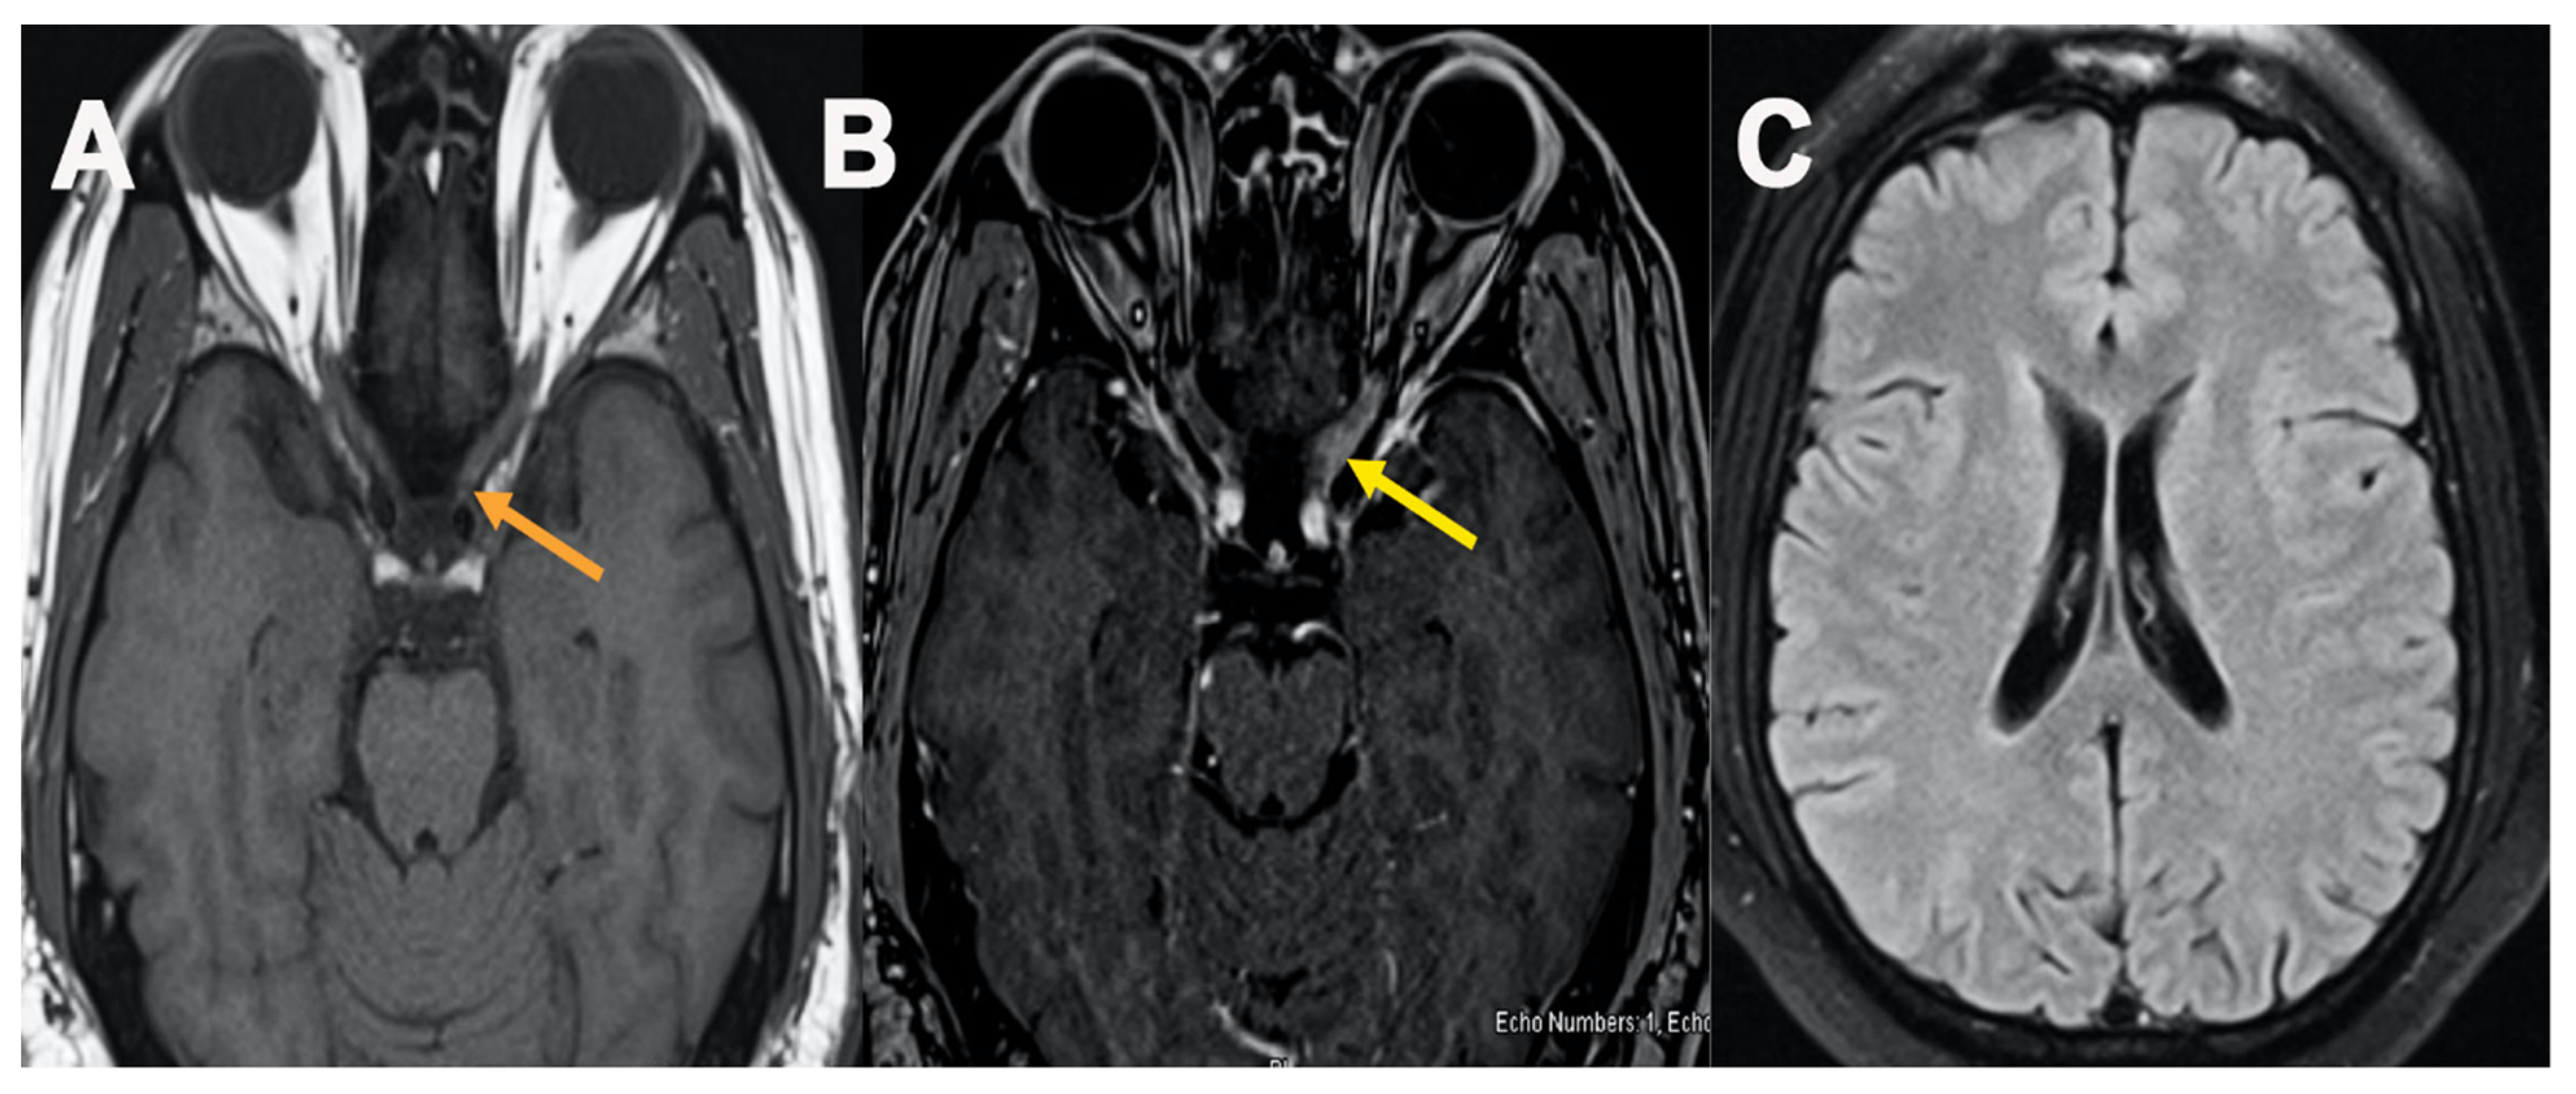

| Keir et al./US [22] | 57 years/F | Pfizer | Post-second dose | Phantosmia | Smelling smoke, hyposmia and headaches | N/A | MRI brain: enhancement of the left greater than right olfactory bulb and bilateral olfactory tracts and hyperintensity in olfactory bulbs and tracts | Normal | CTA no vessel occlusion or aneurysm | N/A | None | Recovered |

| Azam et al./UK [18] | 67 years/M | AstraZeneca | 15 days | GBS BFP variant | progressive worsening of the gait, bilateral leg, bilateral facial weakness, and difficulty in chewing food | CSF Protein: 390 mg/dL Glucose: 86 mg/dL | MRI brain: showed enhancement of the facial nerve bilaterally at the fundus of the internal auditory meatus extending into the labyearsinthine segment | Normal | N/A | N/A | IVIG | Improved |

| Rossetti et al./US [19] | 38 years/M | Janssen | 14 weeks | GBS/BFP | Bilateral hand and foot paresthesias, dysarthria, bilateral facial weakness | CSF Glucose: 73 mg/dL CSF protein: 181 mg/dL Cell Count: 7/mm3 | MRI brain: bilateral internal auditory canal fundi which carry CN-VII and CN-VIII | N/A | N/A | N/A | IVIG | Improved |

| Bayas et al./Germany [29] | 55 years/F | AstraZeneca | 10 days | SOVT | Conjunctival congestion, retro-orbital pain, and diplopia | N/A | MRI brain: Showed superior ophthalmic vein thrombosis (SOVT) | N/A | N/A | N/A | Heparin | Recovered |